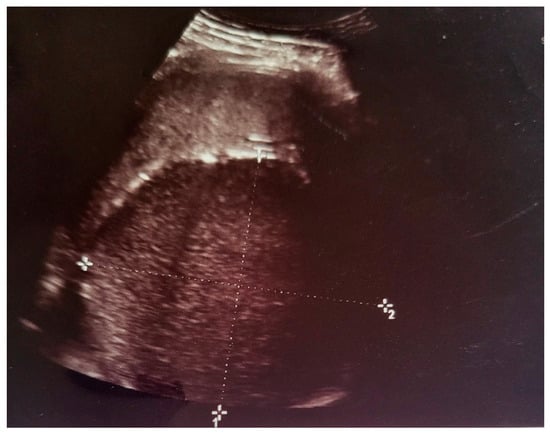

2. Case Presentation

- Grade I splenomegaly with simple voluminous splenic cyst, 10 cm in diameter.

- Accessory spleen adjacent to the lower pole of the spleen.